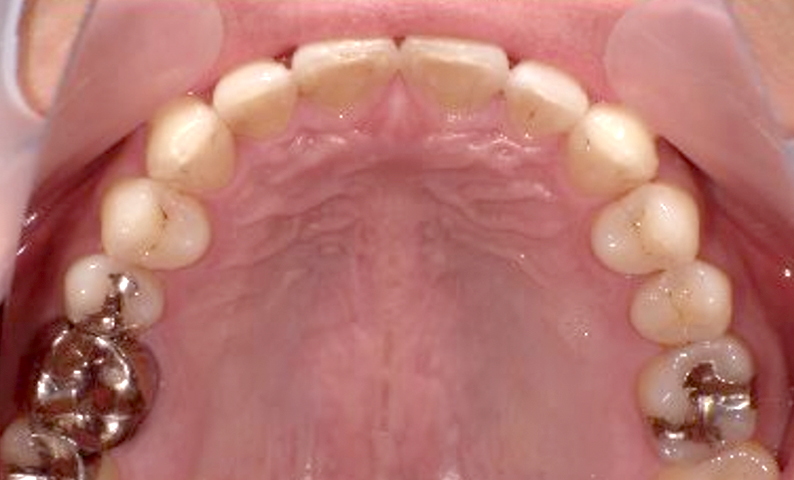

| 治療前 | 治療後 |

|---|---|

|